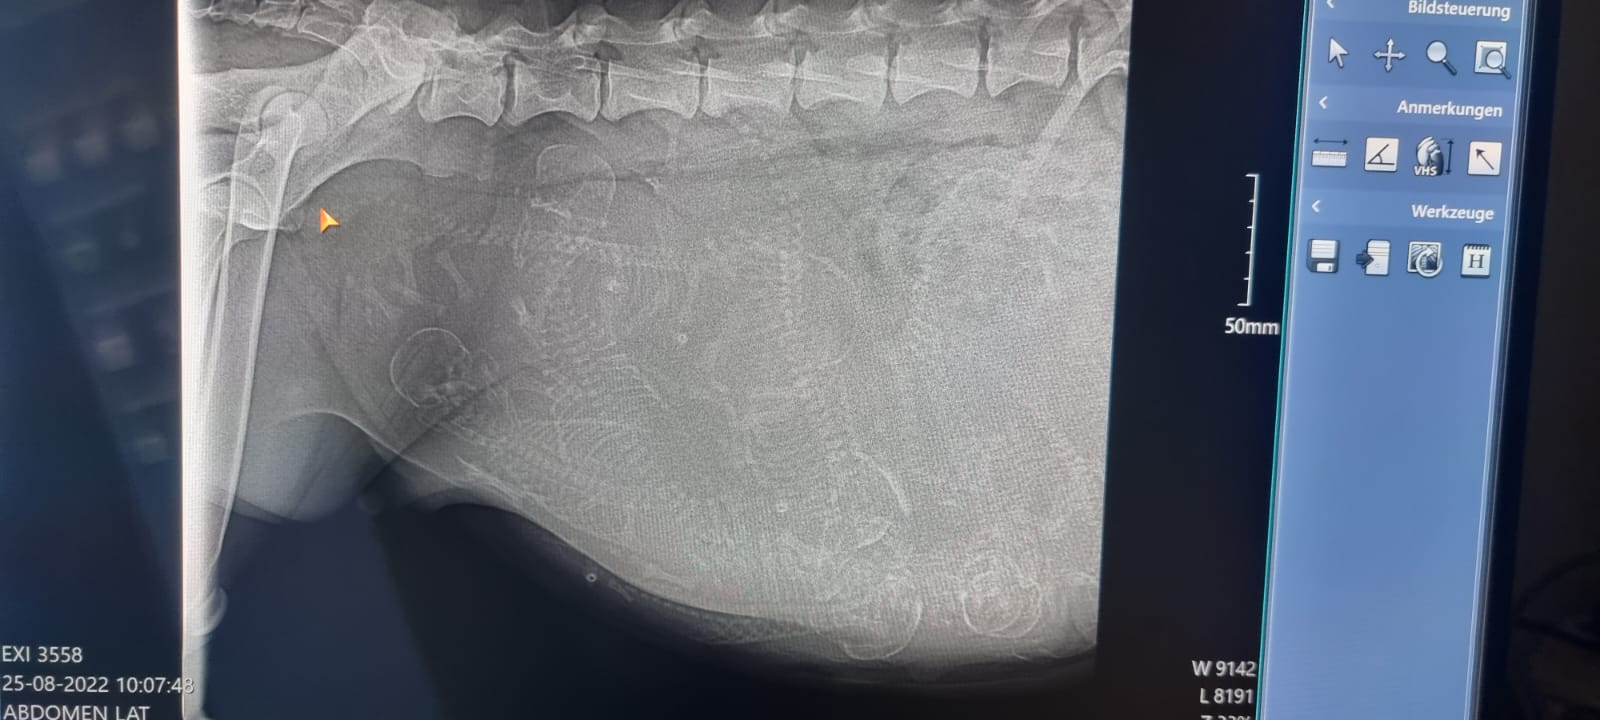

Heute am Tag 55 der Trächtigkeit waren wir mit Bones beim Tierarzt um die obligatorische Röntgenuntersuchung durchführen zu lassen.

Alles ist bestens verlaufen, es werden wohl um die 10 Welpen werden...